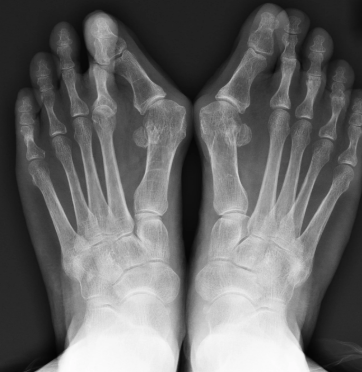

外反母趾関係が多い。

①遺伝

遺伝パワーはすごい。

江戸時代の方にも外反母趾の方は

いました。

靴を履いてなくても、前重心が

すごい家系(大腿骨のねじれ)の場合

それこそ生まれたときからつまさき重心なんで

外反母趾になります。

②重心のクセ

ヒールを履き始めたのが社会人デビューで

そこから20年以上ヒールを履かされ

なんならプライベートでもヒールだった方。

ご自身ではわかりにくいですが

今フラットな靴を履いていても

まあまあの確率で前重心になってます。

20年超のクセはなかなかなんです。

③老化

全員じゃありませんが、過労に伴い

・足周りの筋力低下→外反足

・足裏の脂肪層の激減

・足の握力低下による浮き指

トリプルコンボで指曲がってしまう方も

正直いらっしゃいます。

外反母趾は脱臼+靱帯・神経の固定。

骨を「バキッ」っとやったから直るものではない。